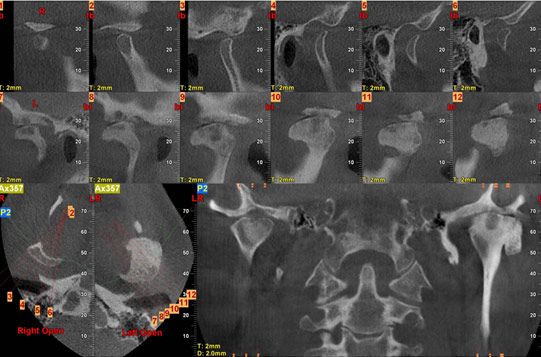

A sagittal series of tomograms (Figure 3) demonstrated a variable opacity with well-formed margins in the left condyle. There was a small ovoid lucency extending through the structure. The head of the mass appeared to extend anteriorly well beyond the fossa.

Figure 3